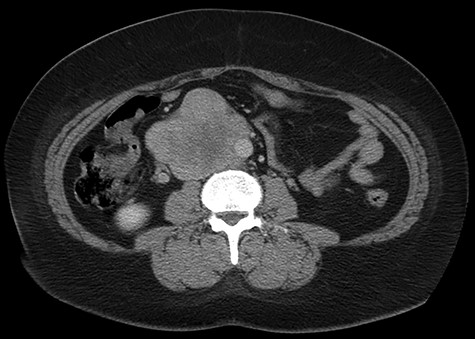

Abdominal CT demonstrating the length and location of the IVC in relation to the aorta.

Abdominal CT demonstrating the location of the tumor in the IVC.

The patient had a body mass index of 40, so combined with her presentation, age and gender. The presumptive diagnosis was of gallbladder pathology, which prompted an abdominal ultrasound. Ultrasound revealed a large 7.7 × 6.3 × 7.2 cm heterogenous, hypoechoic masslike lesion overlying the IVC (Fig 1). Abdominal CT was performed, which revealed an 8.9 × 7.9 × 9 cm multilobulated, heterogeneous soft tissue mass in the right hemiabdomen, encasing the IVC and partially encasing the distal abdominal aorta (Figs. 2–4). CT-guided biopsy was performed, which revealed an LMS.